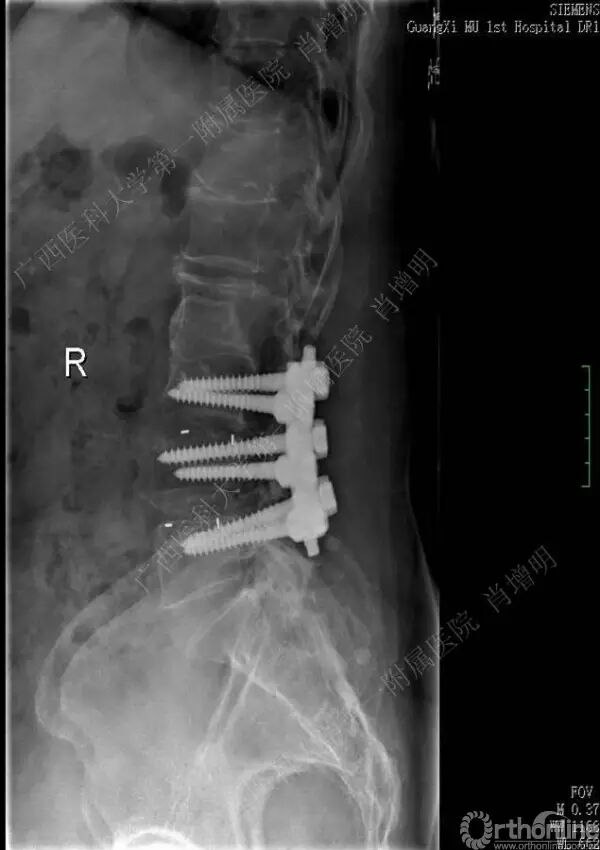

退变性脊柱侧凸是由于椎间盘退变后继发小关节退变,椎管和神经根管容积变化以及脊柱失稳,畸形等病理改变,以疼痛和神经压迫症状为主要表现的常见疾病。

退变性脊柱侧凸多发于50岁以上的中老年群体,是现代常见的老年疾病。多年来,针对该病的临床研究一直没有停步,广西医科大学第一附属医院肖增明教授细致地介绍了该病的诊疗进展。